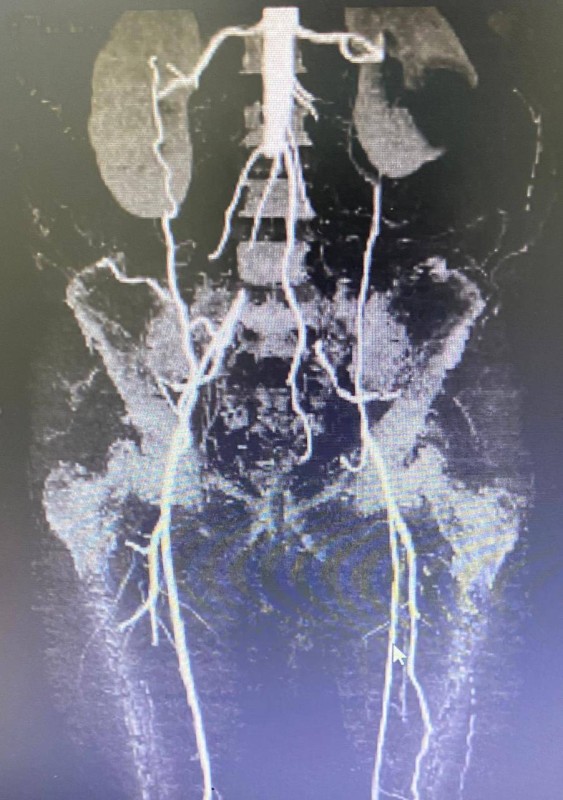

بعد إجراء الفحوصات والتحاليل اللازمة، تبين وجود إنسداد كامل للشريان الأورطي (الشريان الرئيسي في الجسم) بداية من أسفل شرايين الكلى حتى شرايين الحوض، وبعد مشاورات الفريق الطبي ودراسة الحالة، اتُخذ القرار بإجراء القسطرة بدلاً من الجراحة رغم صعوبتها.

وقام الفريق الطبي بالعملية من خلال الدخول بالقسطرة عن طريق شريان الذراع وشرايين الفخذ، بعد ذلك تم فتح الشريان الأورطي بحرص شديد دون أي تأثير على شرايين الكلى أو الأمعاء، وبحمد الله تمت توسعة الشريان ووضع دعامات في الشرايين دون الحاجة للجراحة المفتوحة.